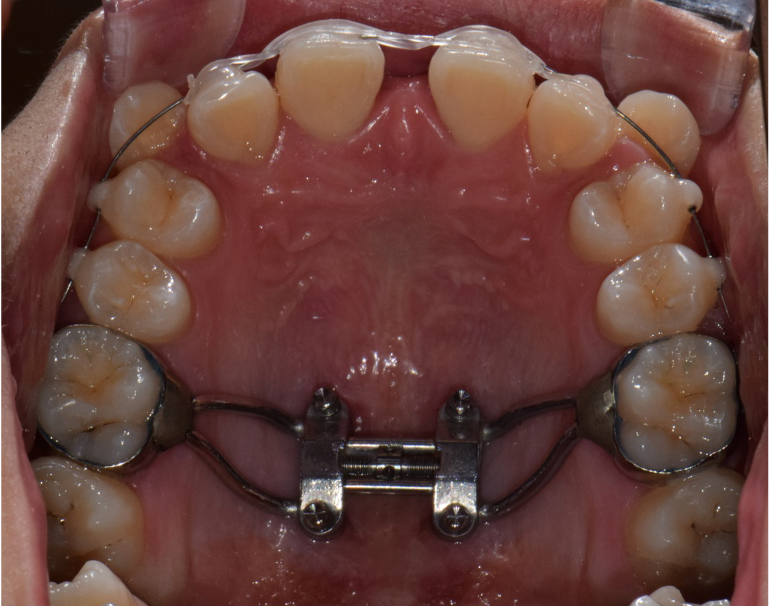

상악 악궁이 좁을 경우에는 하악을 편안하고, 안정적으로 수용하지 못하기 때문에 치아의 배열이 고르지 못하고, 이로 인해 돌출입, 주걱턱과 같은 문제가 생기게 됩니다. 이러한 경우 악궁확장을 통해 미리 증상을 예방하거나 이미 문제가 발생한 경우 시행하여 안정적이고, 바른 치아배열을 만들 수 있습니다. 아래사진은 주걱턱 개선을 위해 양악 수술을 할 줄 알고 큰 근심을 가진 환자를 상악궁 확장을 통한 비수술-비발치 교정으로 치료한 증례입니다.

악궁확장 후 변화

환자의 상태(구개골의 두께, 지대치의 상태 등)를 고려하여 적절한 악궁확장 장치를 사용합니다.